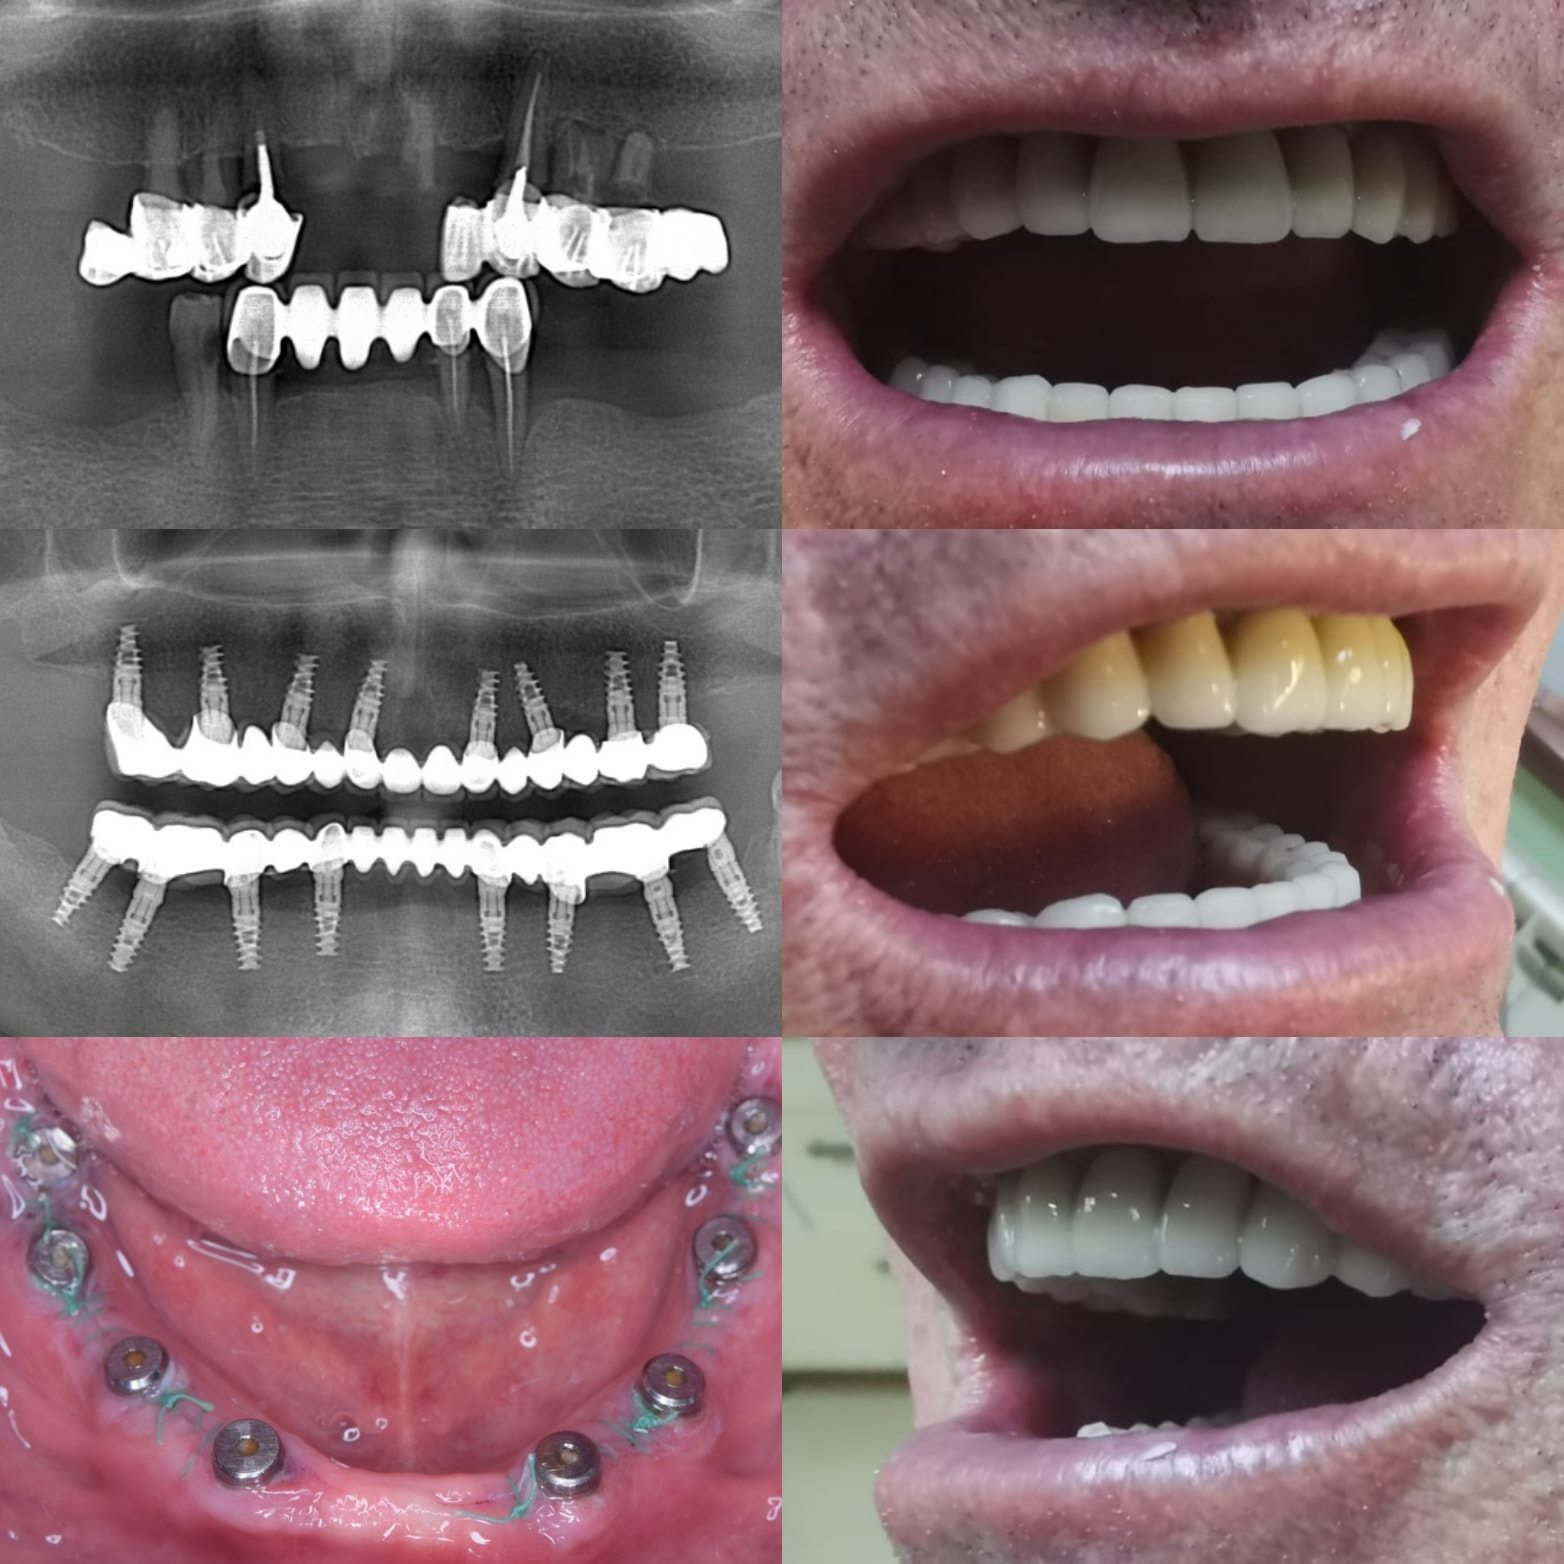

Implanturile dentare sunt dispozitive mici din titan, concepute pentru a înlocui rădăcina naturală a dintelui lipsă. Se inserează în osul maxilar sau mandibular, oferind o bază solidă pentru coroane, punti sau proteze dentare.

• Gândește-te la implanturile dentare All-on-4: Această opțiune inovatoare poate fi o soluție mai accesibilă pentru pacienții care au nevoie de o proteză dentară completă. Implanturile All-on-4 necesită doar 4 implanturi pentru a susține o proteză dentară completă, reducând costul total al tratamentului.